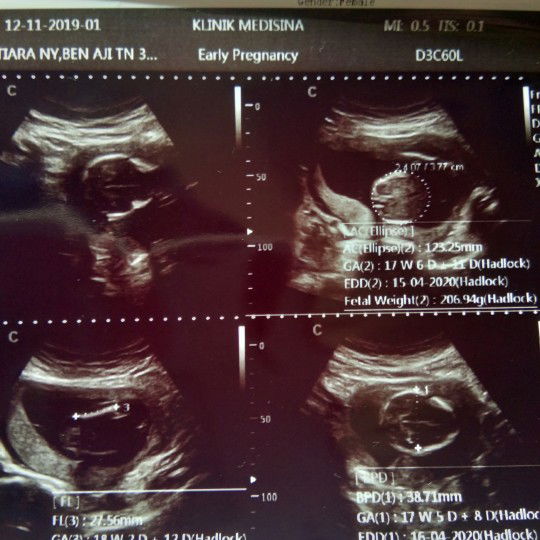

hasil usg

hasil usg sama diaplikasi beda seminggu pdhal saya waktu ditnya sma dktr hari terakhir haid saya kasih tua tgl yg sma